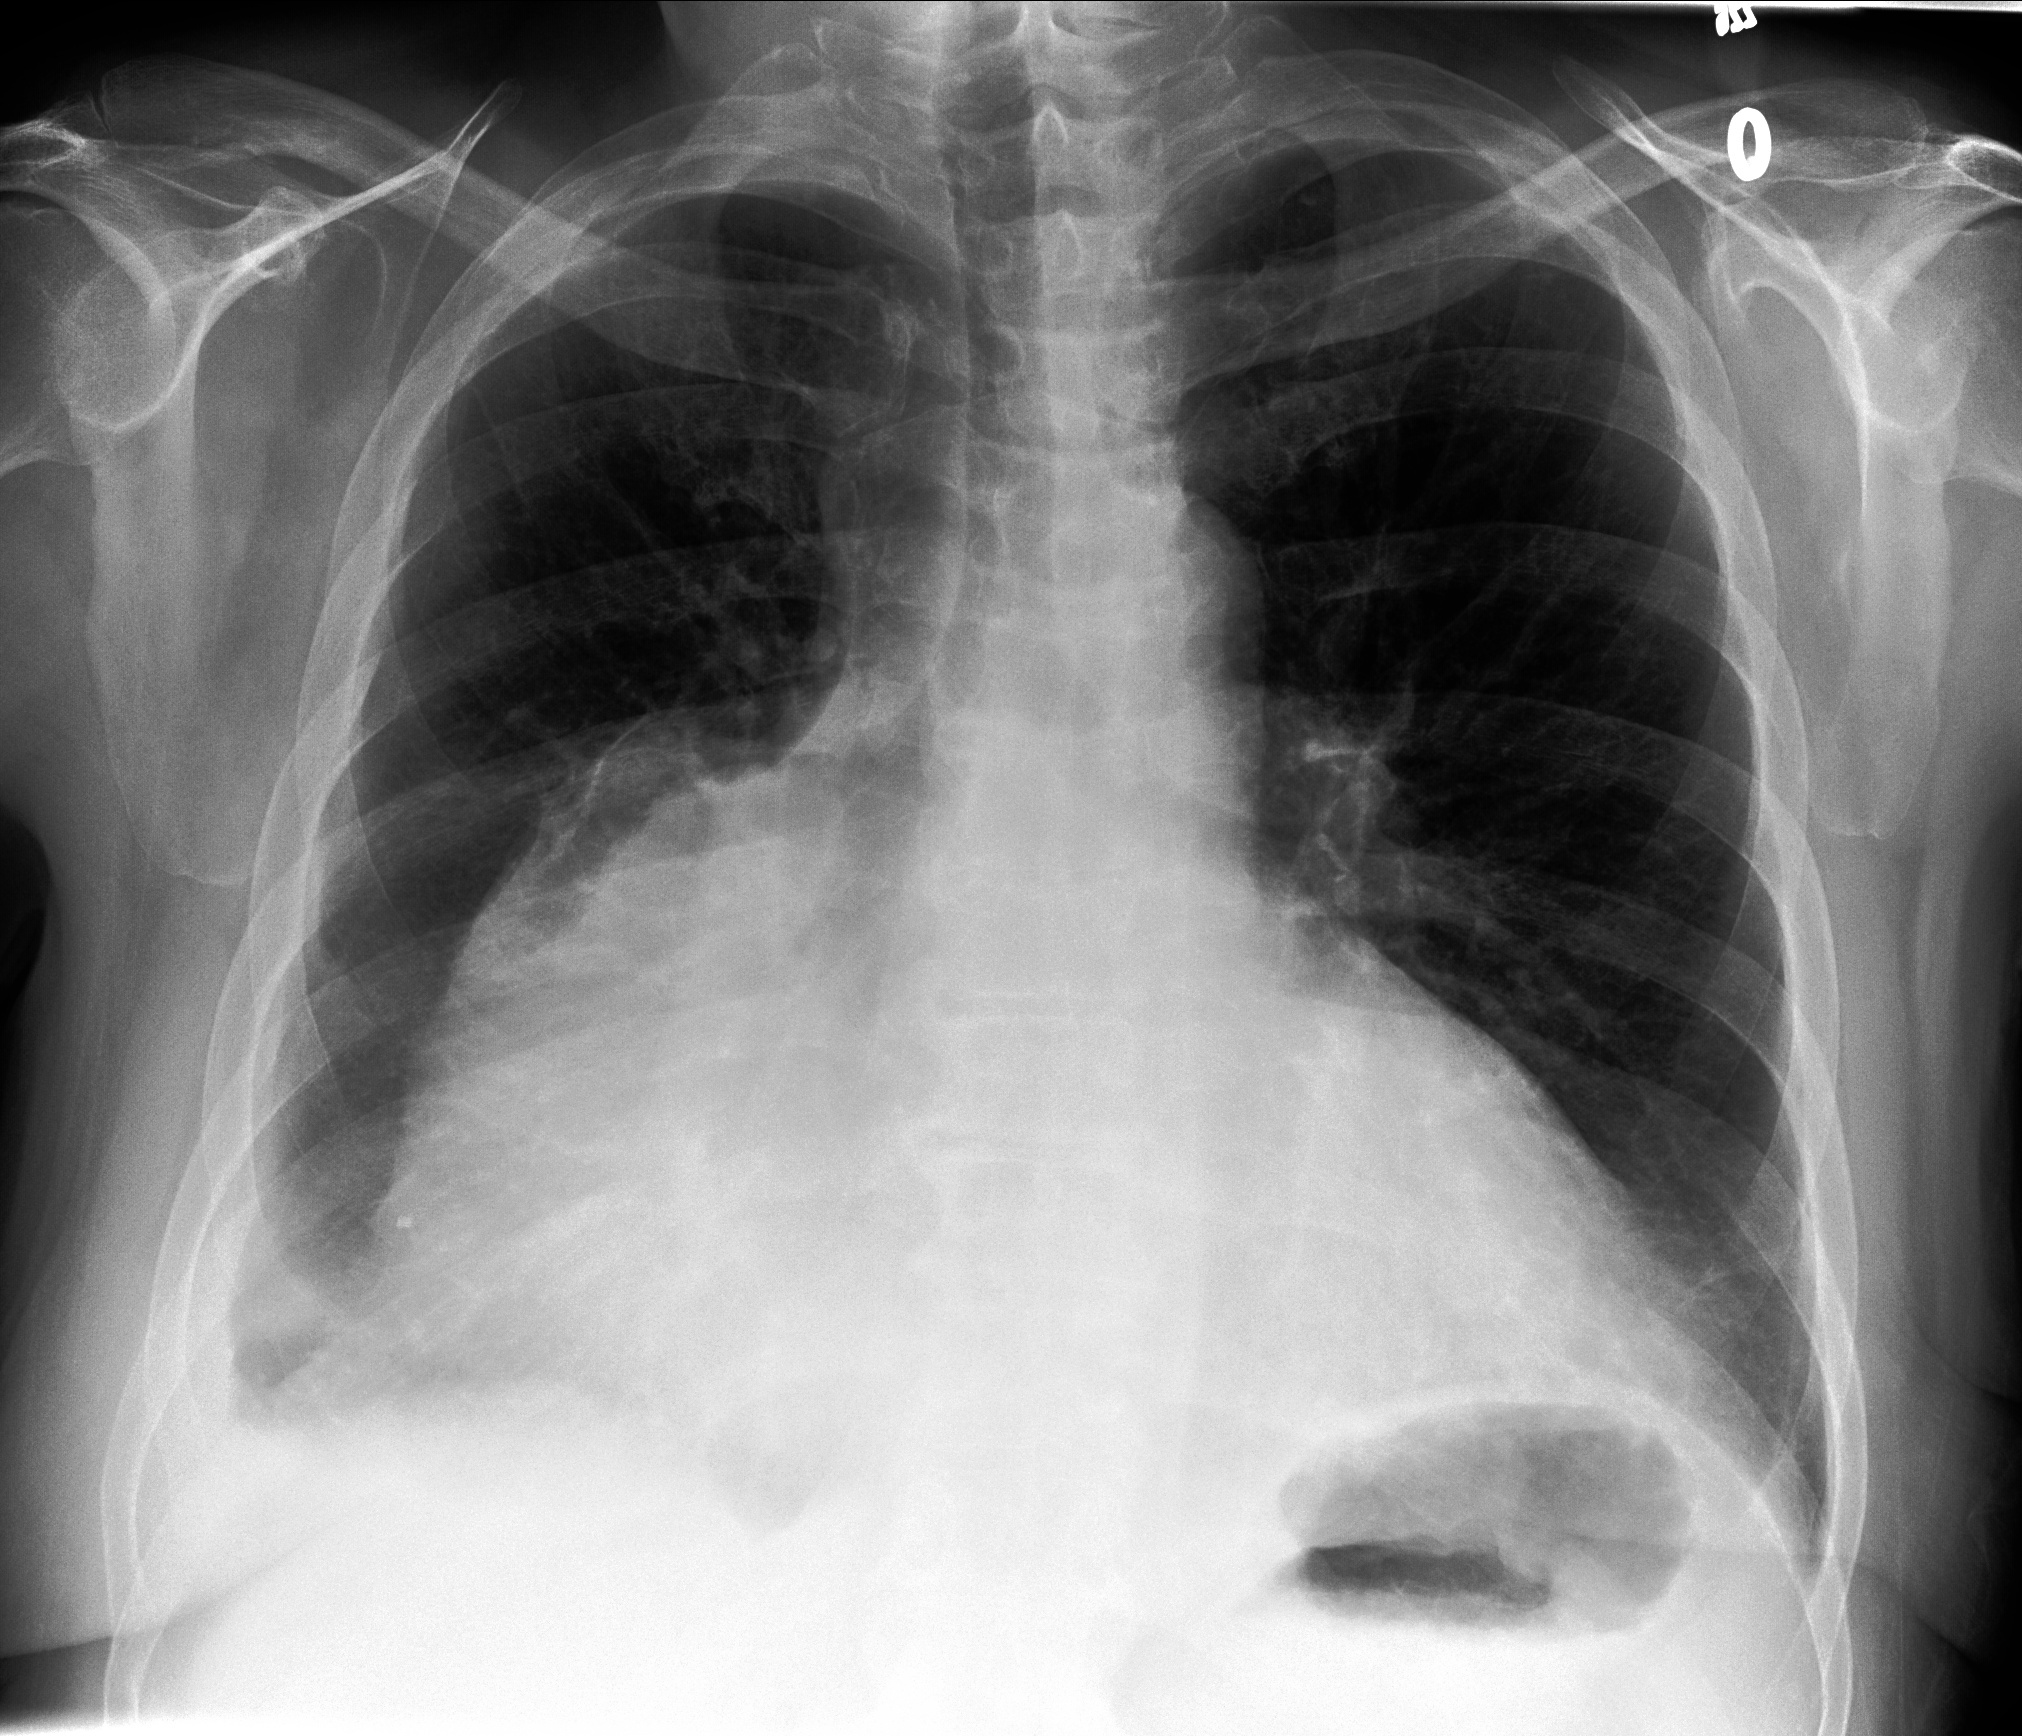

Table 1: Sample chest X-ray (CXR) images. The top row shows a normal CXR, while the remaining rows display CXRs with various pathologies, including right-sided cardiomegaly, large pneumothorax, viral pneumonia, and pulmonary edema.

Normal Chest X-ray Image

[Uncaptioned image]

Right-sided Cardiomegaly Large Pneumothorax

[Uncaptioned image] [Uncaptioned image]

Virus Pneumonia Pulmonary Edema